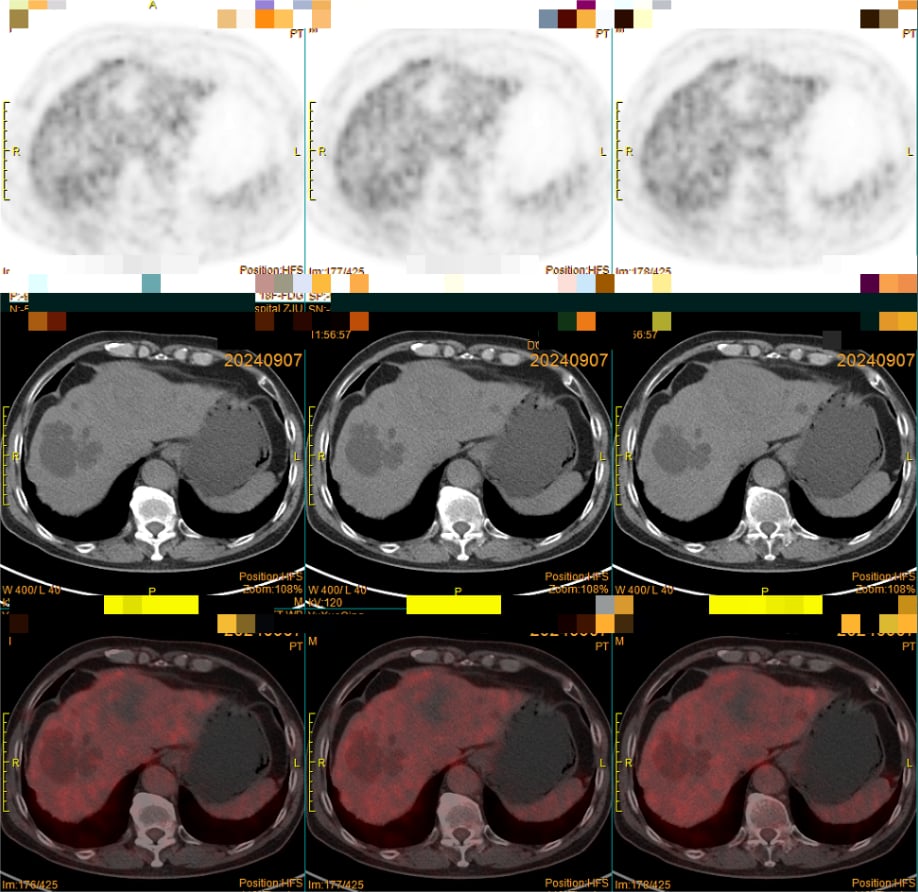

(图3)PET-CT提示:左肝低密度灶,18F-FDG摄取不明显(中央坏死区摄取低于正常肝组织)。

(注:上图病例清晰展示了PET-CT(图3)对高分化肝癌诊断的局限性,而增强MRI(图4)则能根据典型的血流动力学特征做出明确诊断。)